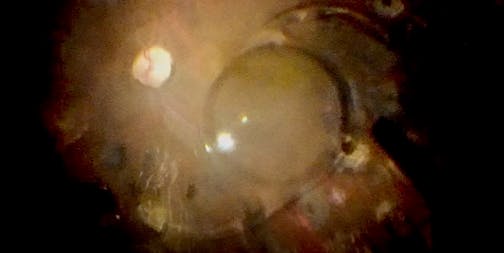

Paul T. Finger, MD, FACS, discusses his experience with intravitreal injections and shares his methods.